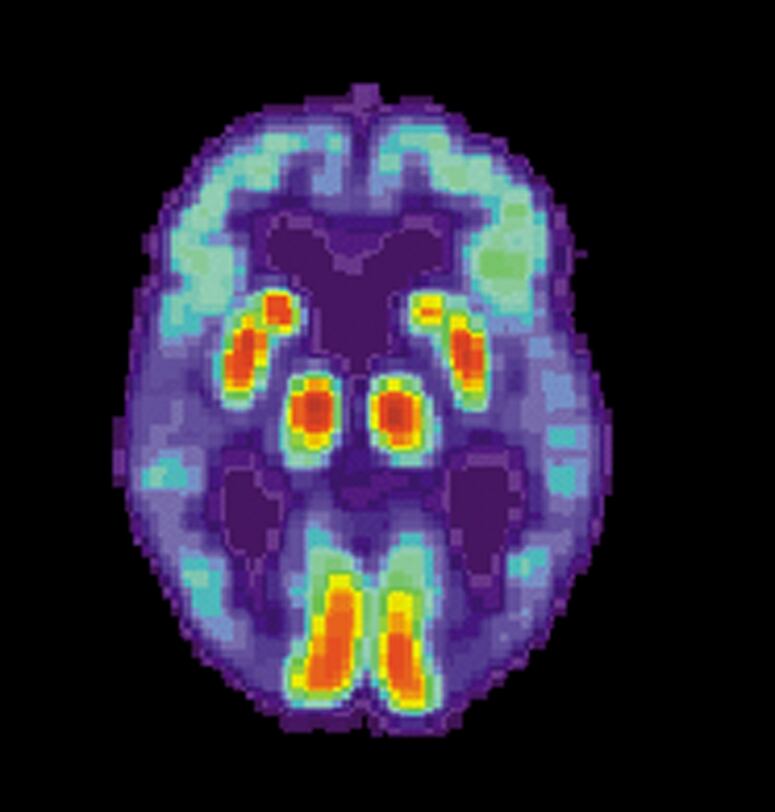

El alzhéimer es un mal neurodegenerativo crónico caracterizado por la pérdida progresiva de la memoria y de la capacidad de quienes lo padecen para realizar actividades básicas.